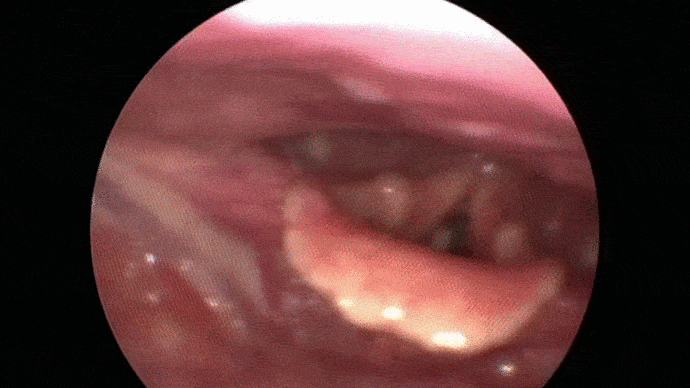

Les troubles de la voix sont analysés puis les cordes vocales sont examinées grâce à système optique afin de proposer une prise en charge adaptée.